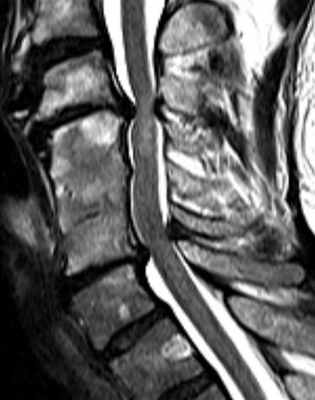

Неврологическая симптоматика в виде нарушения поверхностной чувствительности в правой ноге появилась впервые в апреле 2016 года, спустя 2 года после верификации лимфомы Ходжкина и проведения вышеописанного курса комплексного лечения. Заболевание носило прогрессирующий характер, в течение месяца присоединилась слабость в ногах, тазовые нарушения. Магнитно-резонансная томография (МРТ) грудного отдела позвоночника выявила МР-картину деформирующего спондилеза, остеохондроза, жировую дегенерацию костного мозга, МР-признаки участков миелопатии в спинном мозге на уровне сегментов C5-Th1. Данных, доказывающих опухолевое или метастатическое поражение спинного мозга и его оболочек, не было выявлено. По месту жительства проходила повторные курсы неспецифической метаболической терапии по поводу «миелопатии» (без эффекта). С лета 2016 года присоединилась слабость в левой руке. Проведена МРТ шейного отдела (июль 2016 г.): МР-картина постлучевой спондилопатии C2-Th4 позвонков, миелопатии с уровня C5-Th3. Признаки межпозвонкового остеохондроза шейного отдела позвоночника, протрузии дисков С4-С5, С5-С6. Таким образом, в начале дифференциально-диагностического поиска, по данным МРТ исследования из круга дифференцируемых заболеваний удалось исключить компрессионные повреждения спинного мозга (грыжи дисков, экстрадуральные опухоли, в том числе и лимфому центральной нервной системы), прогрессирование основного заболевания с вовлечением цНс. Первичная спинальная эпидуральная неходжкинская лимфома встречается крайне редко, предпочтительно поражается по-яснично-крестцовый отдел позвоночника, сопровождаясь компрессией спинного мозга.

В диагностике очаговых поражений спинного мозга и в частности, радиационной миелопатии, ведущая роль в настоящее время отводится МРТ. Однозначных нейровизуализационных характеристик для лучевой миелопатии не существует. В доступной нам литературе мы встретили описание нескольких наблюдений, без гистологического подтверждения [8]. МРТ изменения включают в себя области низких сигналов на Т1-взвешенных изображениях, высокочастотных сигналов на Т2 с контрастным усилением. Высокоинтенсивный сигнал на Т2 связан с отеком и сливающимся некрозом, а контрастное усиление является следствием нарушения гематомиелического барьера [11].

ного отдела позвоночника, спинного мозга с контрастированием (01.2017 г.): выявлено прогресси-рование очаговых изменений за время наблюдения (существенное увеличение протяженности с момента исследования от апреля 2016 г., формирование зоны некроза с момента исследования от июля 2016 г.). Учитывая прогрессирующее течение, пациентке начат курс иммуносупрессивной терапии (митоксан-трон), проведен курс внутривенной иммуноглобу-линотерапии. Достигнута стабилизация процесса в течение 1 месяца, продолжается динамическое наблюдение.